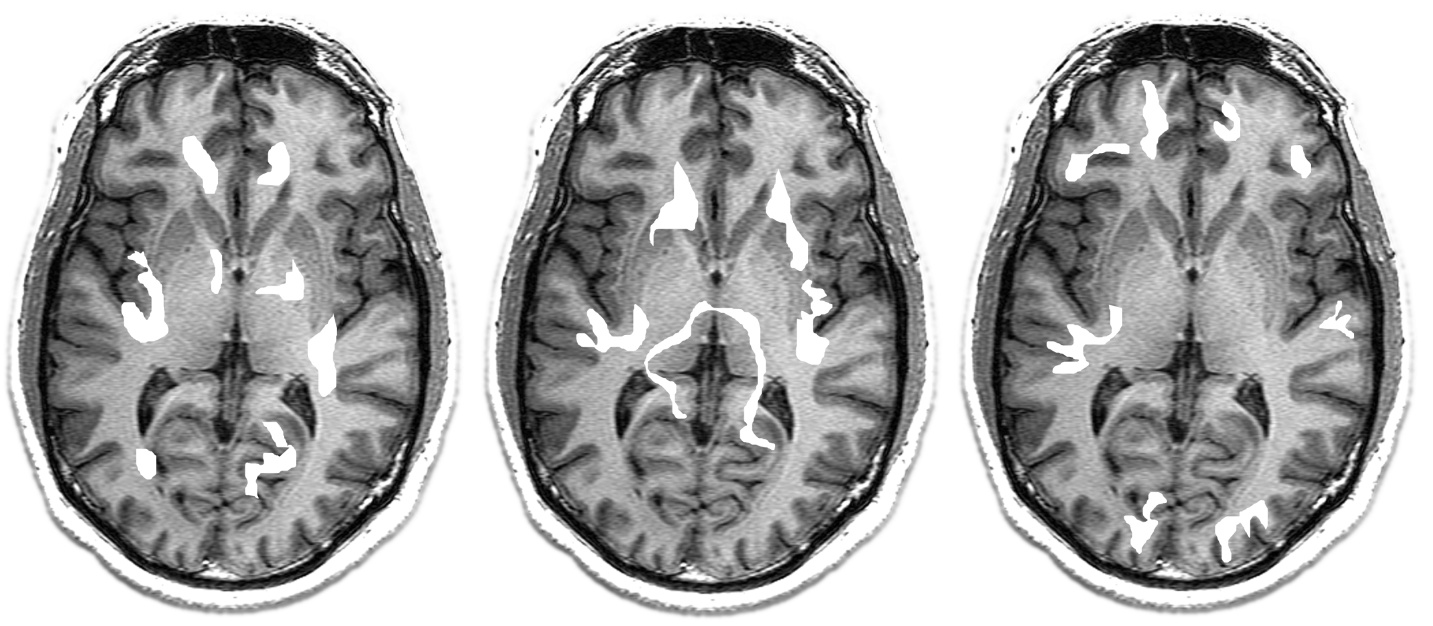

Current neuroimaging measures substrate-level activity (Levels 2-3) that correlates with but does not constitute the conscious simulation (Level 5). A decoder — knowledge of the brain's "programming language" — would bridge this gap. Developing this decoder is a concrete research programme that follows from the theory's architecture.

Axial fMRI slices showing activation patterns. These images illustrate the measurement problem: the highlighted regions indicate where blood oxygenation has changed (Level 2 measurement), which correlates with neural activity — but the conscious content these activations correspond to remains inaccessible without the decoder. The same activation pattern could underlie different phenomenal experiences in different contexts.